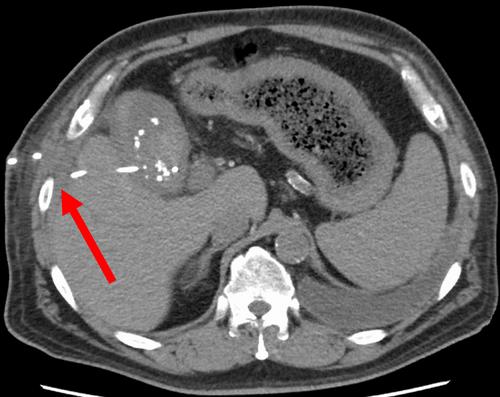

Percutaneous transhepatic gallbladder drainage and percutaneous transhepatic cholangiodrainage are effective therapeutic options for biliary disease, although they occasionally result in thoracic complications. We report two cases of thoracic complications that developed after biliary drainage and were successfully treated using video-assisted thoracoscopic surgery. The first case involved a 55-year-old man who developed a chest wall (extrapleural) abscess after percutaneous transhepatic gallbladder drainage and laparoscopic cholecystectomy. Video-assisted thoracoscopic surgery revealed an extrapleural abscess that was initially diagnosed as empyema. The second case involved a 71-year-old woman who developed bilious pleural effusion after percutaneous transhepatic cholangiodrainage. Video-assisted thoracoscopic surgery was used to identify and close a diaphragmatic fistula. Both patients had a favorable postoperative course. This report demonstrates that video-assisted thoracoscopic surgery can be an effective therapeutic approach for thoracic complications after percutaneous biliary drainage.